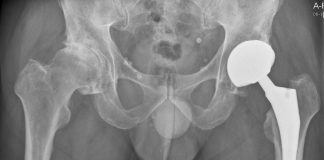

Ingreep heupprothese kan prima poliklinisch

Gezonde patiënten met artrose die in aanmerking komen voor een heupprothese, kunnen die ingreep heel goed in dagbehandeling ondergaan. Dat blijkt uit onderzoek van...